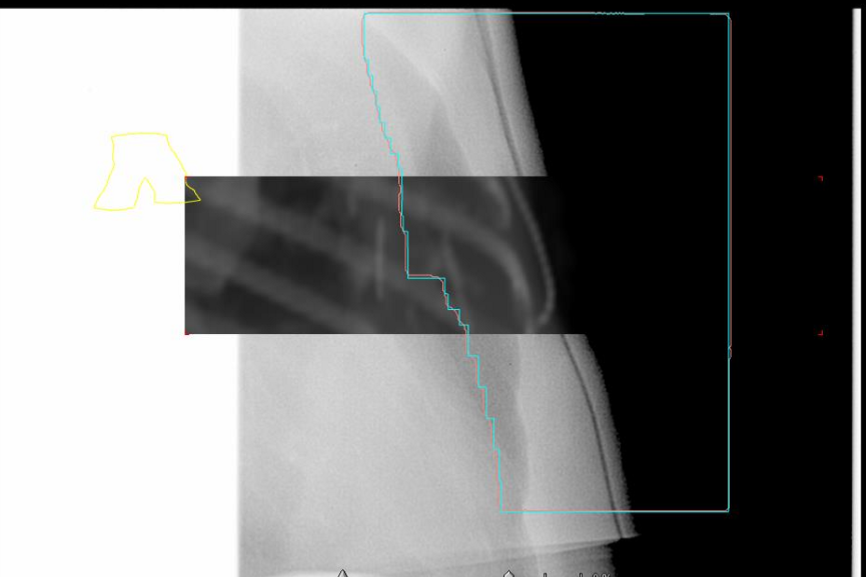

what are the two ways to evaluate the lung inclusion within the MLC?

use moving window and make lung match

don’t use moving window and just look at where the apex of the lung hits the posterior border of the contour

when doing our medial BEV check for a chest wall patient? what are two things we are looking for

we want to check the posterior MLC, making sure there is same amount of lung in each

also we want to do a bolus assessment to see it is conforming nicely